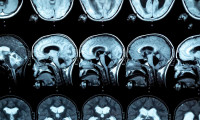

Статті про здоров’я

Розсіяний склероз (РС) — це патологічний стан, що супроводжується ураженням центральної нервової системи.

Гідроцефалія - це патологічний стан, що супроводжується накопиченням спинномозкової рідини в порожнинах мозку з наступним його набряком.